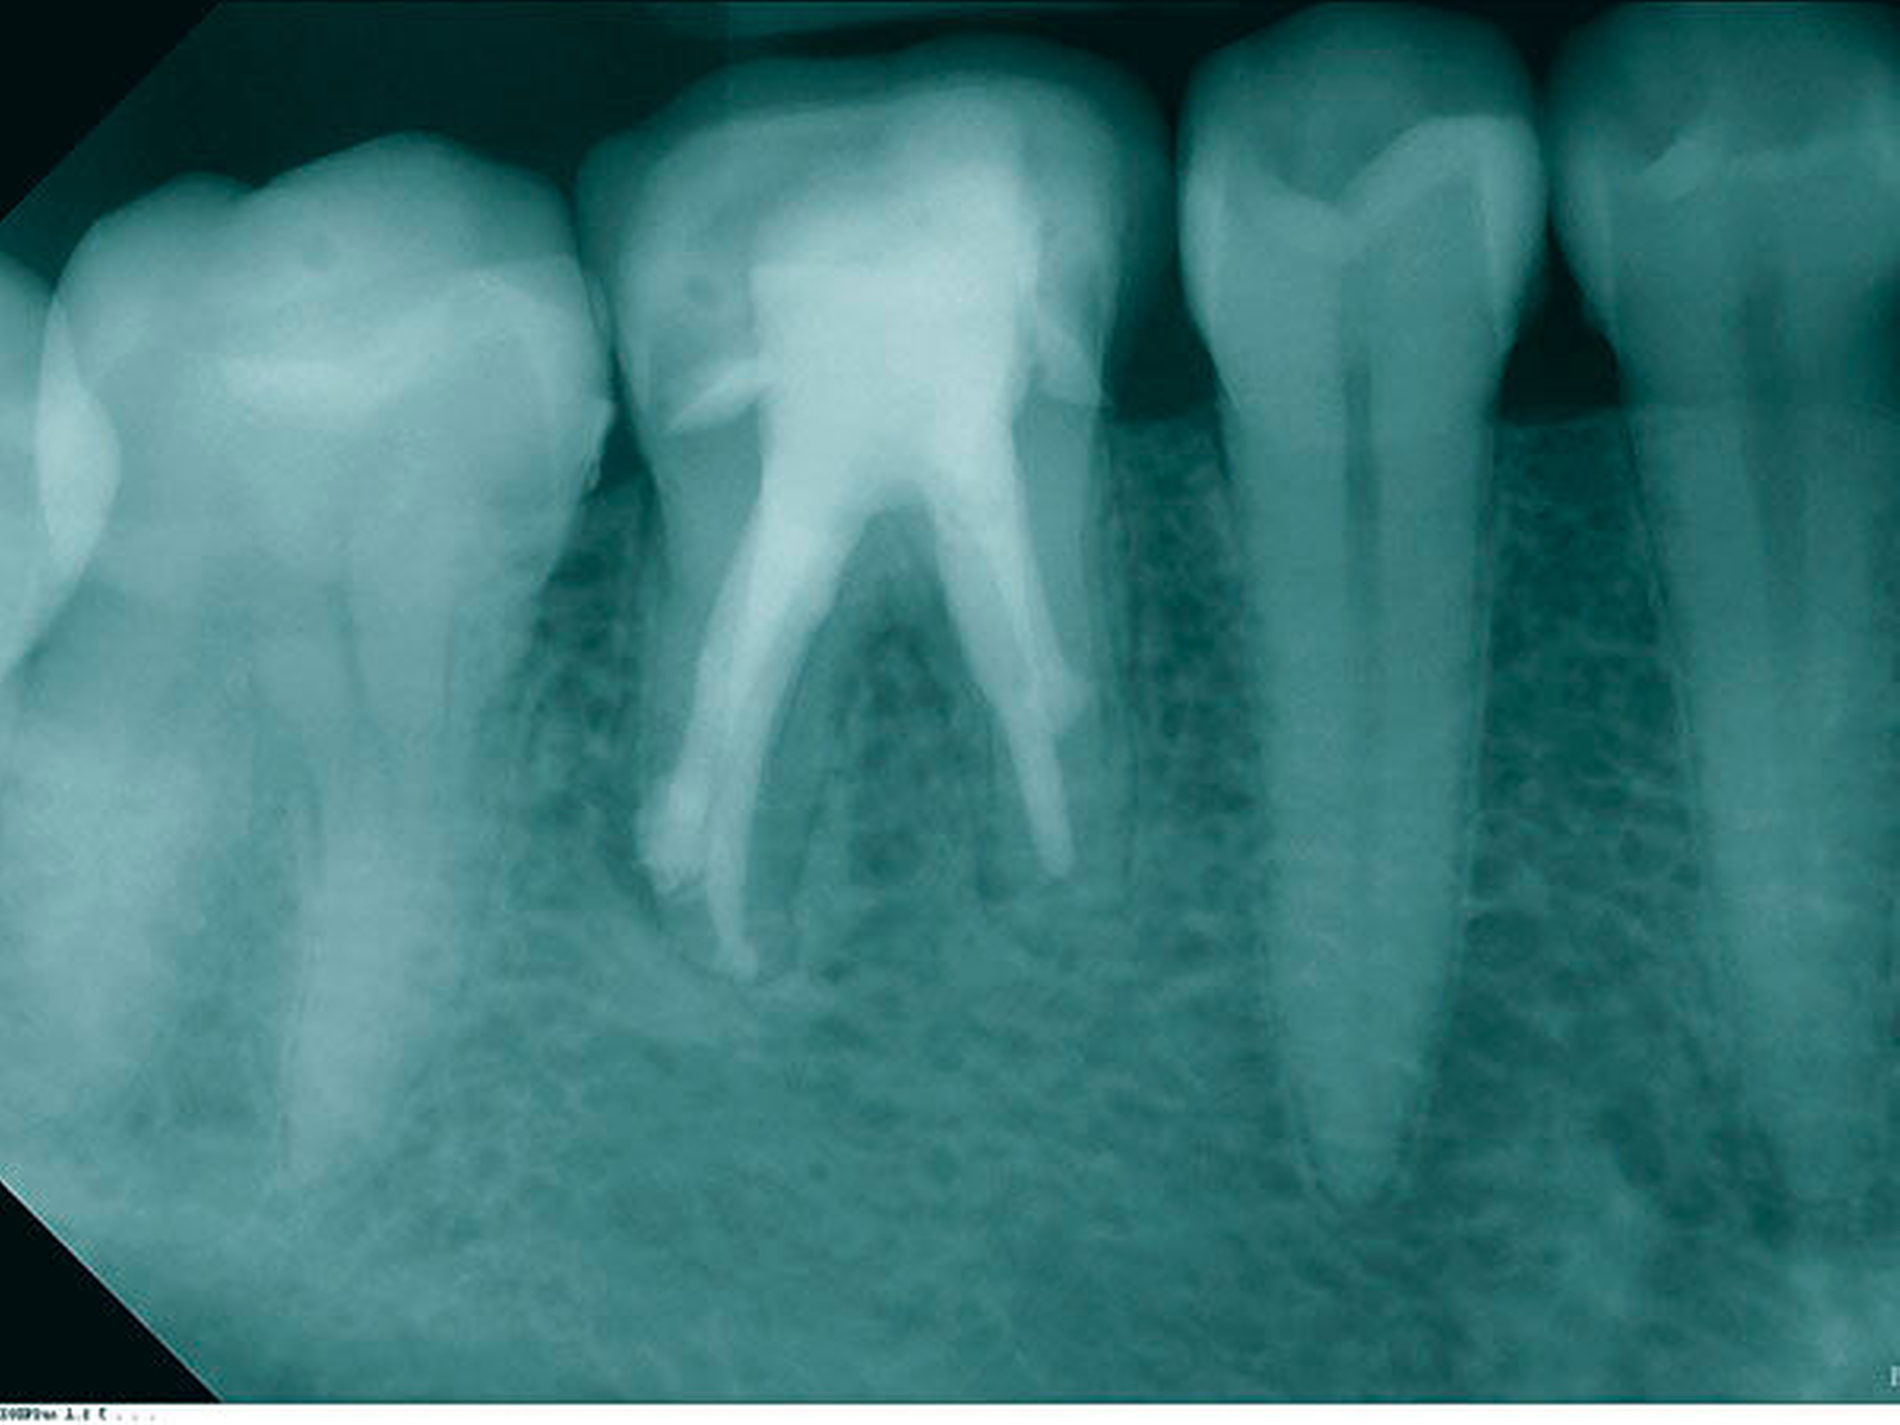

In der ersten Therapiesitzung erfolgte – nach Isolierung mit Kofferdam – die Trepanation des Zahnes und die Stiftentfernung mit Ultraschallinstrumenten. Im Anschluss wurden die drei gefüllten Kanäle revidiert, der vierte, nicht abgefüllte, mesiobukkale Kanal dargestellt und präpariert. Die elektronische Längenmessung ergab 14,5 mm für den mesiobukkalen Kanal, 17,0 mm für den mesiolingualen, 15 mm für den distobukkalen und 16 mm für den distolingualen. Aufgrund der großen initialen Kanaldurchmesser und der guten Einsicht bis ins periapikale Gewebe (Abbildung 2) wurde auf eine Längenmessaufnahme verzichtet. Die Desinfektion erfolgte mit Natriumhypochlorid (NaOCl) 5 Prozent und EDTA 17 Prozent, sowie Schallaktivierung mittels EDDY-Spitzen (VDW, München). Das Wurzelkanalsystems wurde manuell mit K-Feilen bis IS0 70 präpariert. Es folgte eine medikamentöse Einlage mit AH Temp (DentsplySirona, Bensheim). Danach wurde eine Aufnahme zur Kontrolle der vollständigen Guttapercha-Entfernung und der suffizienten Einbringtiefe des Kalziumhydroxids angefertigt (Abbildung 3).